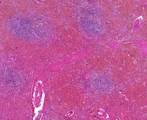

![]() | zwyrodnienie amyloidowe śledziony ogniskowe | 0%